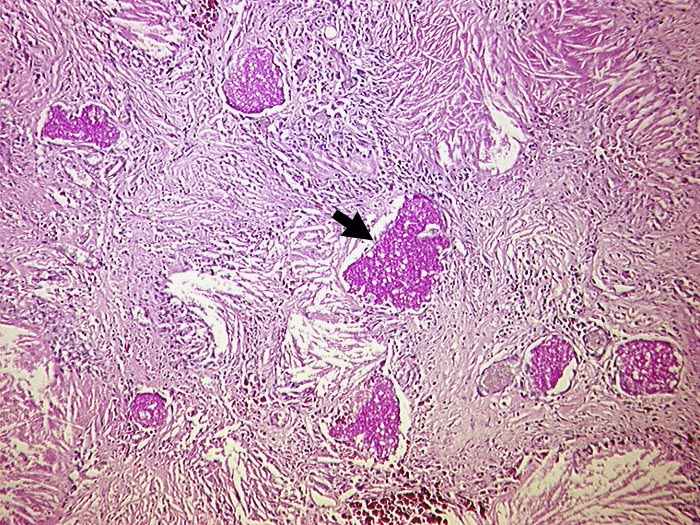

Vernarbung des Lungeninterstitiums mit herausgelösten Cholesterinkristallen und ► PAS positiven schaumigen Einschlüssen. Diese enthalten zahlreiche Erreger.

AIDS. HIV Positivität bekannt seit 2 Jahren bei iv Drogenabusus.